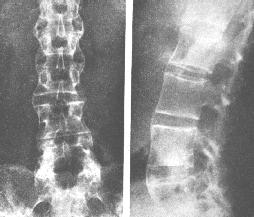

强直性脊柱炎诊断方法哪些

强直性脊柱炎诊断方法是什么?强直性脊柱炎是一种十分常见的症状,患上强直性脊柱炎会时时…[详情]